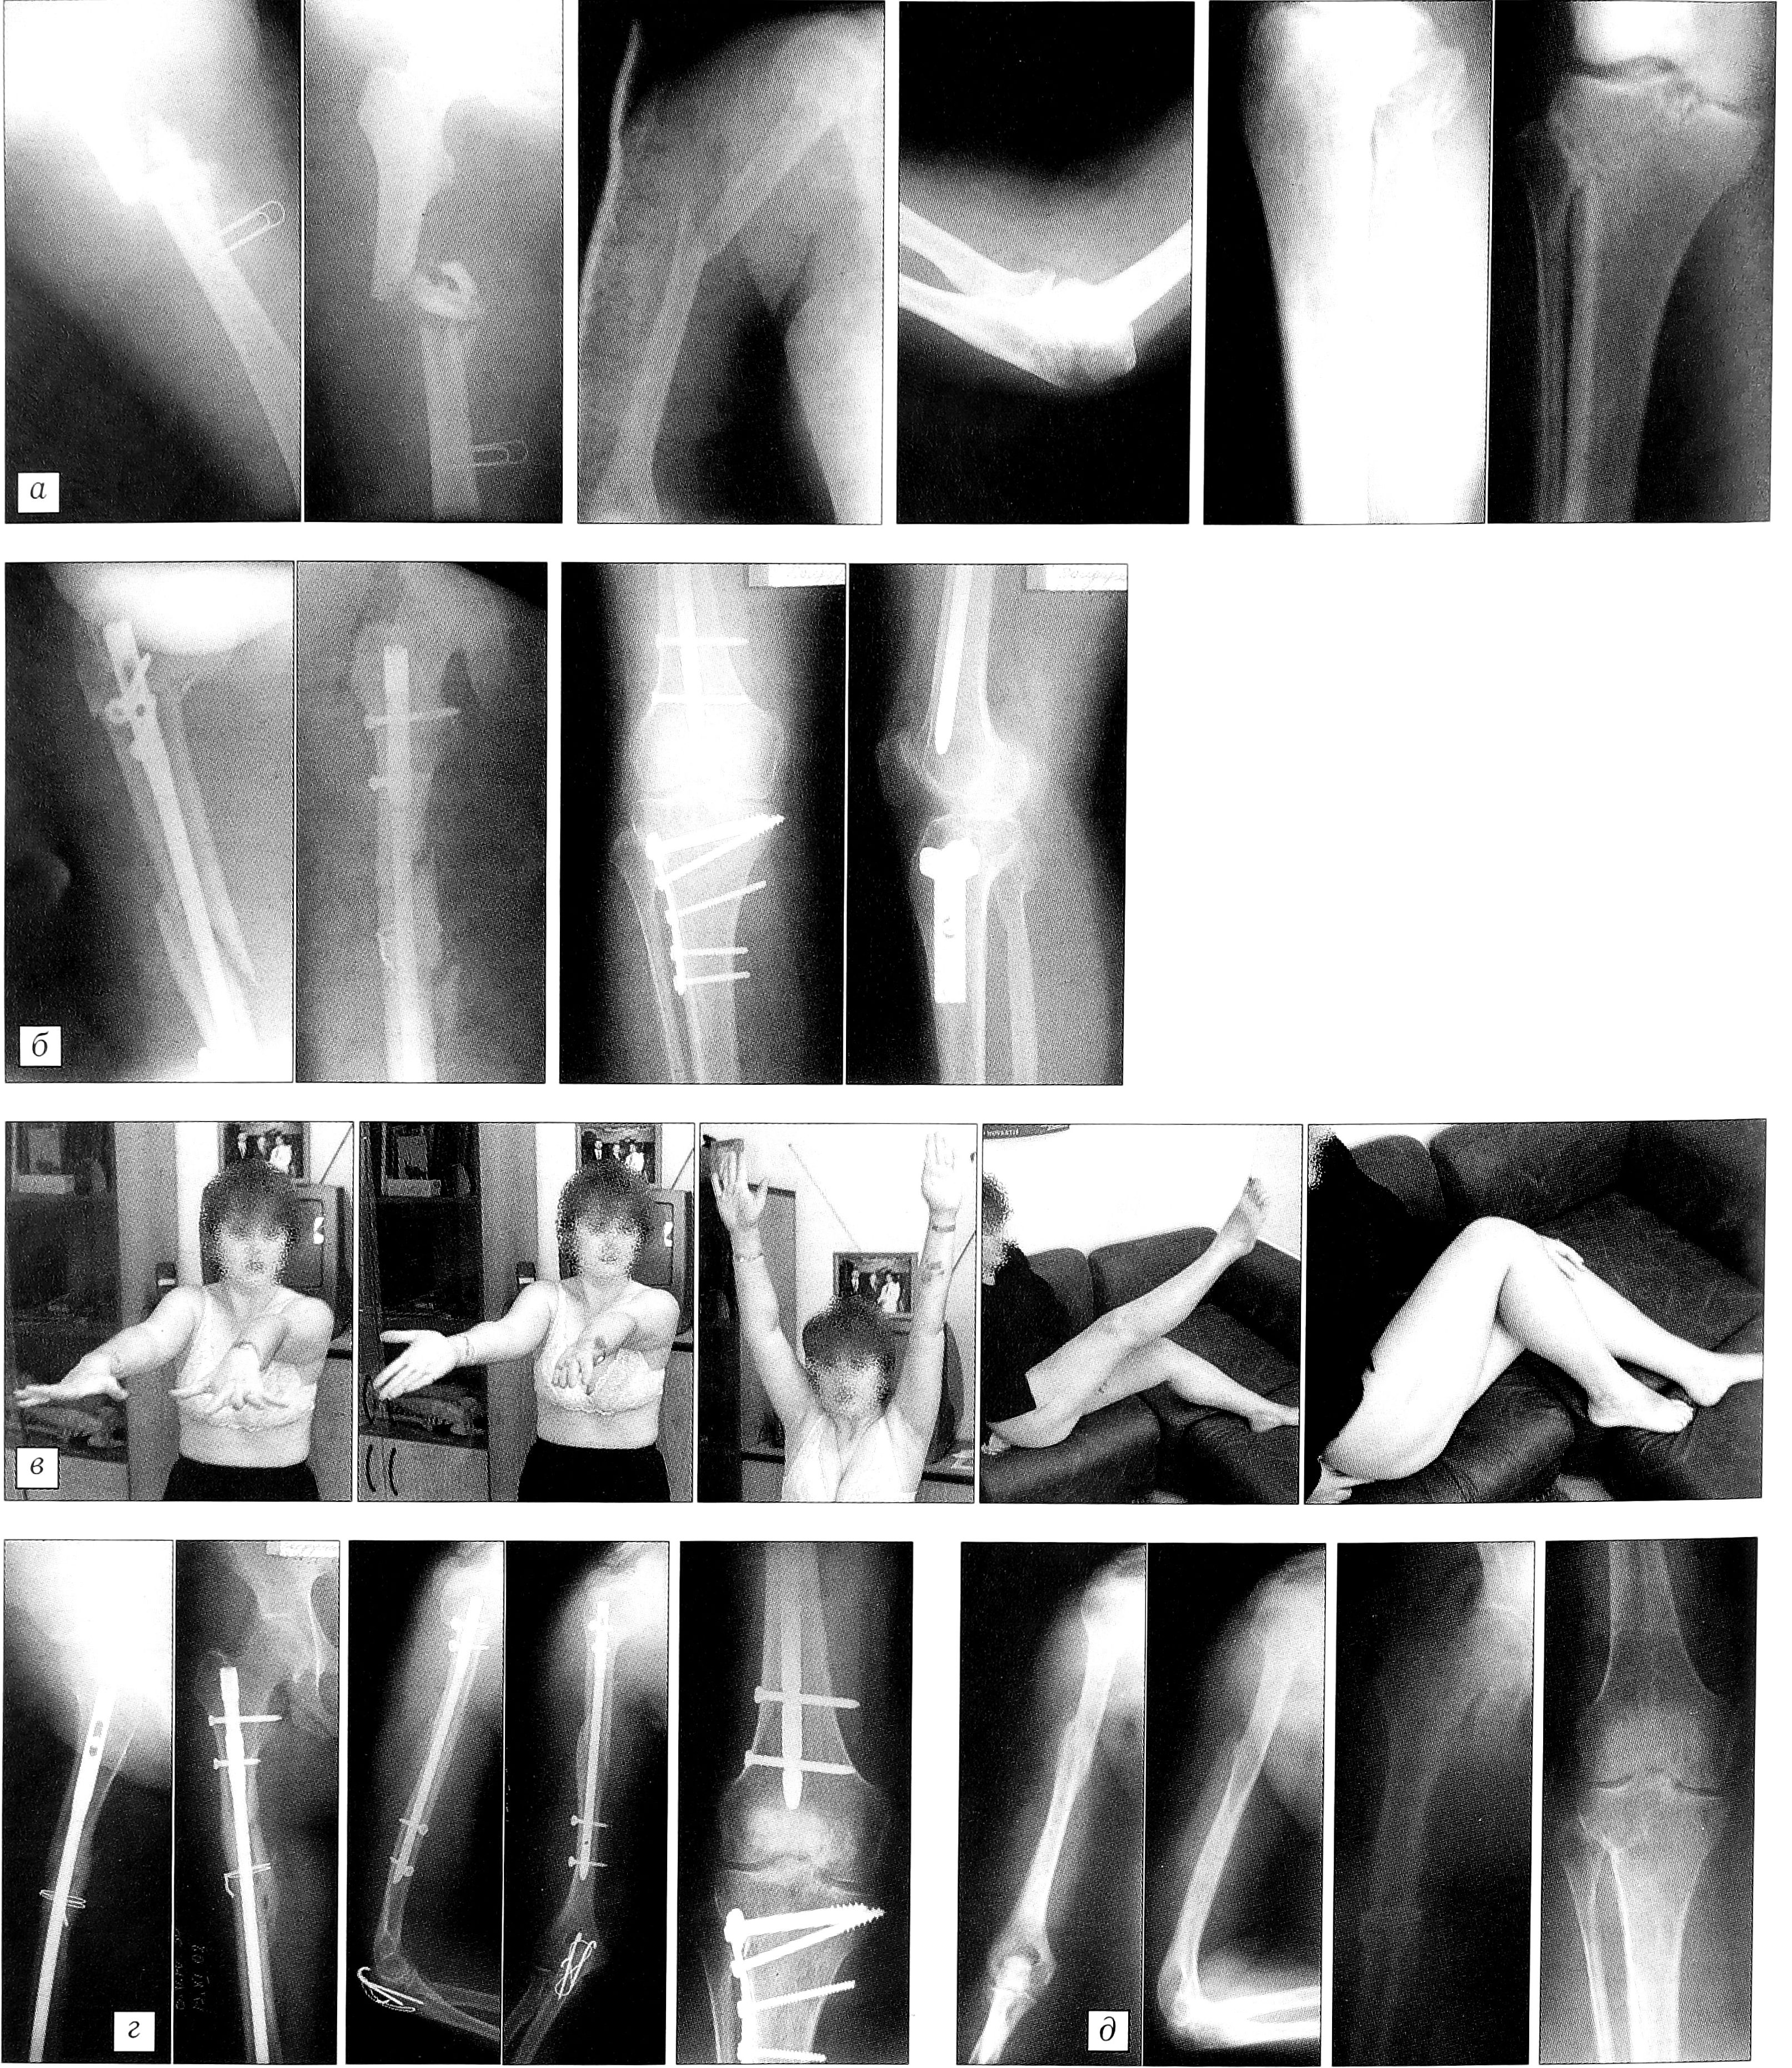

Пример. Больная Б.,30 лет,8.07.01 в результате ДТП получила перелом средней трети правой бедренной кости, средней трети и хирургической шейки правой плечевой кости, перелом локтевого отростка справа (имелся парез лучевого нерва справа), импрессионный перелом наружного мыщелка правой большеберцовой кости (рис. 1, а). Через 5 дней после травмы была госпитализирована в ЦИТО, где 18.07.01 произведен одновременный остеосинтез правой бедренной кости стержнем UFN, правой плечевой кости стержнем UHN, остеосинтез локтевого отростка по Веберу, остеосинтез наружного мыщелка правой большеберцовой кости Т-образной опорной пластиной (рис. 1, б). На 2-е сутки после операции больная активизирована, проводилась терапия прозерином, витаминами группы В. Через 3 нед после операции пациентка выписана на амбулаторное лечение. На момент выписки ходила при помощи костылей с ограниченной нагрузкой на правую ногу. Через 4 мес после операции двигательная активность была полностью восстановлена (рис. 1, в). Через 1 год 8 мес рентгенологически констатировано сращение всех переломов, металлоконструкции удалены (рис. 1, г, д).

Рис. 1. Больная Б. Диагноз: перелом средней трети правой бедренной кости, средней трети и хирургической шейки правой плечевой кости, перелом локтевого отростка справа, импрессионный перелом наружного мыщелка правой большеберцовой кости. а — рентгенограммы при поступлении; б — после выполнения остеосинтеза; в — функциональные возможности через 4 мес после операции; г — рентгенограммы через 1 год 8 мес после операции: сращение переломов; д — после удаления металлофиксаторов.